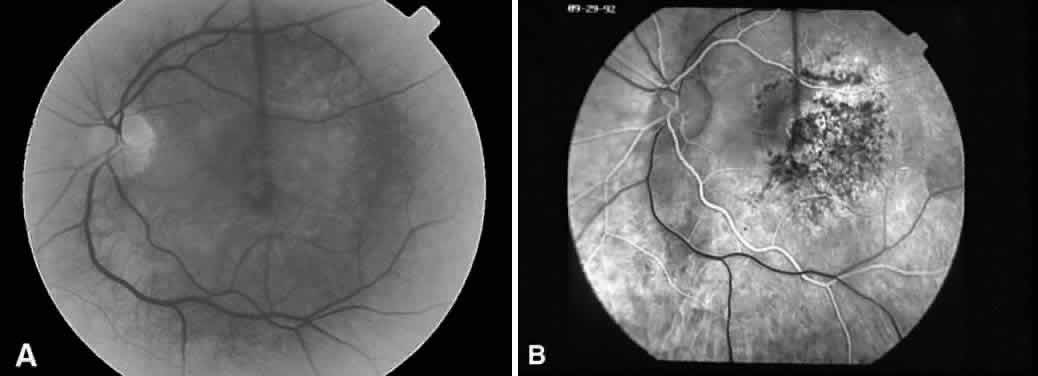

Recognizing light toxicity in the posterior segment may be difficult and is under reported because the findings can be extremely subtle on examination and many cases are asymptomatic. However, clinical features of such lesions are now well described, and when they occur in a high-risk situation, a diagnosis usually can be made. An accompanying fluorescein angiogram (Fig. 2) or visual field test can support a diagnosis if clinical suspicion is high.

Fig. 2. A. Fluorescein angiography of a 49-year-old patient with a malignant melanoma on the left iris who consented to deliberate induction of photic retinopathy by the operating microscope before scheduled enucleation of that eye. Red-free photograph of the normal posterior pole of the left eye pre-exposure. B. Late phase of the angiogram, pre-exposure, demonstrates a normal macula. C. Red-free photograph of the left eye after light exposure showing a vertically oriented lesion centered in the macula. D. Late phase of the angiogram demonstrates hyperfluorescence in the area of photic damage. (Green WR, Robertson DM: Pathologic findings of photic retinopathy in the human eye. Am J Ophthalmol 112:520, 1991)

Tso divides photic injury into three phases: acute, reparative, and chronic degenerative.16 Clinically, immediately after the insult, there is no sign of disease, but a temporary blood-retinal barrier dysfunction can be detected by the use of fluorophotometry, as reported by Borsje and associates.74 Again, from a clinical standpoint, the first sign of retinal phototoxicity may be seen within 24 to 48 hours by mild pigmentary changes, retinal edema, or both.16 After 1 week, focal pigment epithelial change becomes more visible. Little change is noted clinically in the reparative phase. After the first month, the lesions generally become smaller. Pigmentation is variable, ranging from subtle depigmentation to marked hyperpigmentation and frank retinal pigment epithelial hyperplasia.16,75,76 Five-year follow-up on Tso's work has shown chronic decompensation of the blood-retinal barrier as a long-term consequence of light-induced retinal injury.8